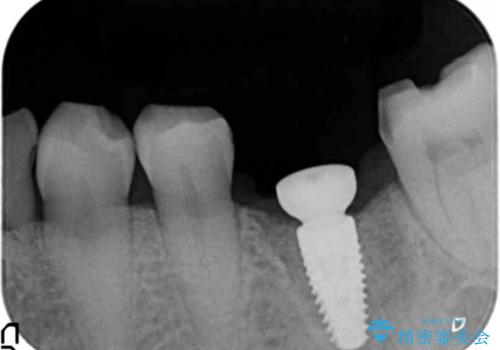

強い噛み合わせによる歯牙破折後のインプラント治療

ブリッジや入れ歯といった周囲の歯の負担を増やす方法ではなく、より強大な咬合力にしっかりと耐え噛むことのできるインプラントを用いた機能回復を計画します。

- 34万円(税別)(ストローマンインプラント・アバットメント・仮歯・フルジルコニアクラウン)費用は治療当時の料金となります